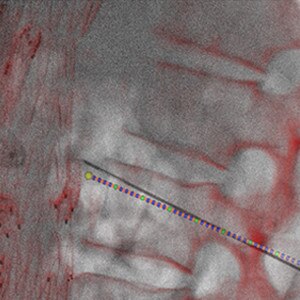

1 -La solution NEEDLE ASSIST inclut TrackVision 2 et Stereo 3D ; elle requiert le poste de travail AW équipé de Volume Viewer et Volume Viewer Innova. Ces applications sont vendues séparément.